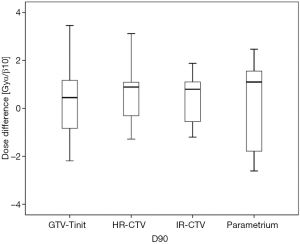

Among the 23 patients included in the present study, the mean tumor diameters were 68.35 cm3 at diagnosis and 29.63 cm3 at ICBT initiation. The mean tumor regression was 56.6%. The mean ± standard deviation (SD) HR-CTV D90 and D100 of the GTV-Tinit, IR-CTV, and parametrium were 69.58±4.94, 61.89±3.53, 54.16±4.01, and 55.71±2.73 Gyα/β=10, respectively, for DIR and 69.11±5.68, 61.55±4.15, 53.99±3.93, and 55.51±2.27 Gyα/β=10, respectively, for the conventional simple DVH parameter addition (Figures 3-5). No statistically significant differences were observed in the dosimetric parameters between the two calculation methods (Table 2). No systematic differences were observed between DIR-based accumulation and DVH parameter addition (P=0.11).

Contouring and reconstruction performed in the same image series allowed the dose to targets and organs to be directly calculated without any image fusion. However, the fusion uncertainties could translate into absorbed dose calculation when several image series were combined. For example, contouring was performed in one image series and reconstruction in another. Tanderup et al. reported that uncertainties resulted in a miscalculation of DVH dose parameters by typically 4% to 6% mm−1 of fusion error between CT and MRI (18). van Heerden et al. (19) recently used DIR to determine the absorbed dose distribution of daily image-guided adaptive EBRT and brachytherapy. The cone-beam CT of the first EBRT fraction and the brachytherapy planning MRI were registered by DIR. The cumulative dose to 2 cm3 with the highest dose (D 2 cm3) from EBRT and brachytherapy to the bladder and rectum were calculated and compared to those for direct addition, assuming a uniform EBRT dose (UD). The differences between UD and DIR were less than 3.9 GyEQD2. Our study only used CT images with the same field of view and slice thickness for fusion. The DIR-based DVH parameter values did not differ significantly from those derived from the conventional simple DVH parameter addition (Figure 3). According to the Groupe Européen de Curiethérapie and the GEC-ESTRO recommendations (10), the conventional simple DVH parameters for the target volumes and OARs in EBRT and each ICBT session were simply added to estimate the cumulative DVH parameters.